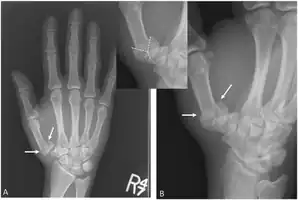

The cause is generally a force along the long axis of the thumb, such as during a fight.[3][4] Diagnosis is by medical imaging; such as X-ray, CT scan, or MRI.[3] It results in at least three bone fragments, which often form a T- or Y-shaped pattern.[3][4] It differs from a Bennett fracture which only results in two bone fragments.[4]

'Y-shaped' Rolanda fracture